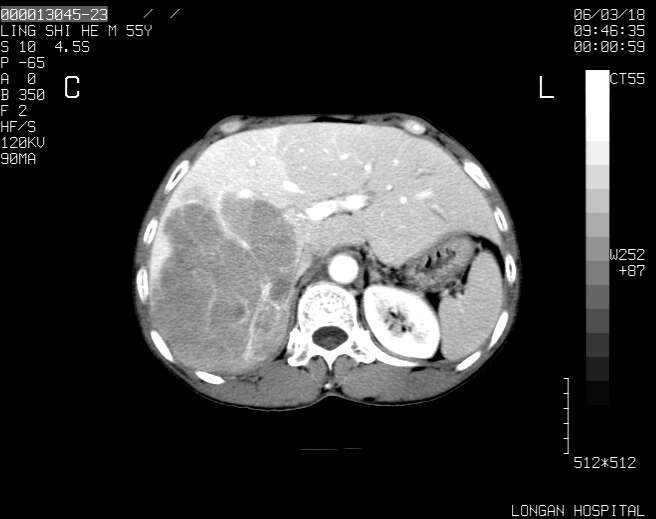

以下是引用guzhongliangddd在2006-3-21 22:13:00的发言:[br]病灶主要位于肝右叶的后份,内见异常血管,门脉主干及右支受侵{提示有癌栓形成},门腔间隙内见增大淋巴结。肝左叶内未见异常。

以下是引用zhuxinli在2006-3-22 1:23:00的发言:[br][br] 病灶主要位于肝右叶的后份,内见异常血管 .门脉右支截断,右叶前段早期强化(考虑动静脉漏),腹膜后肿大淋巴结,病灶逐渐强化,考虑为胆管细胞癌[br]